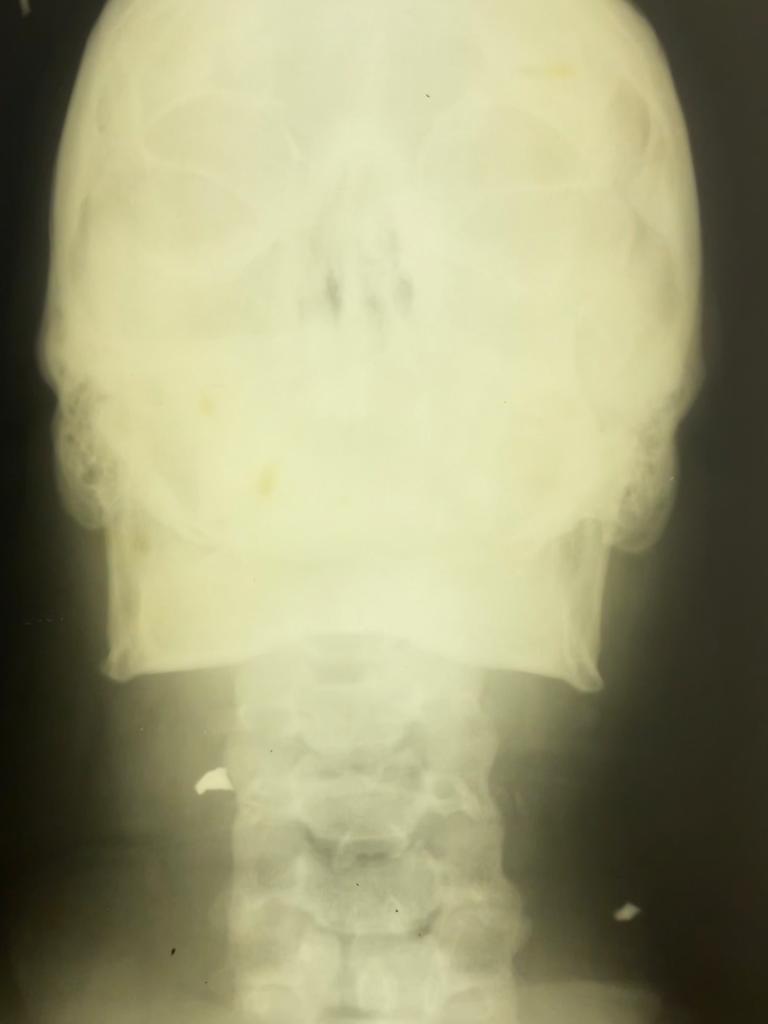

Рис. 2. Инородное тело в области подъязычной кости (рентгенограмма, прямая проекция).

Fig. 2. A foreign body in the area of the hyoid bone (X-ray, direct projection).

На рентгенограммах шеи от 30.11.23 г. определяется ИТ в области подъязычной кости (рис 1,2).